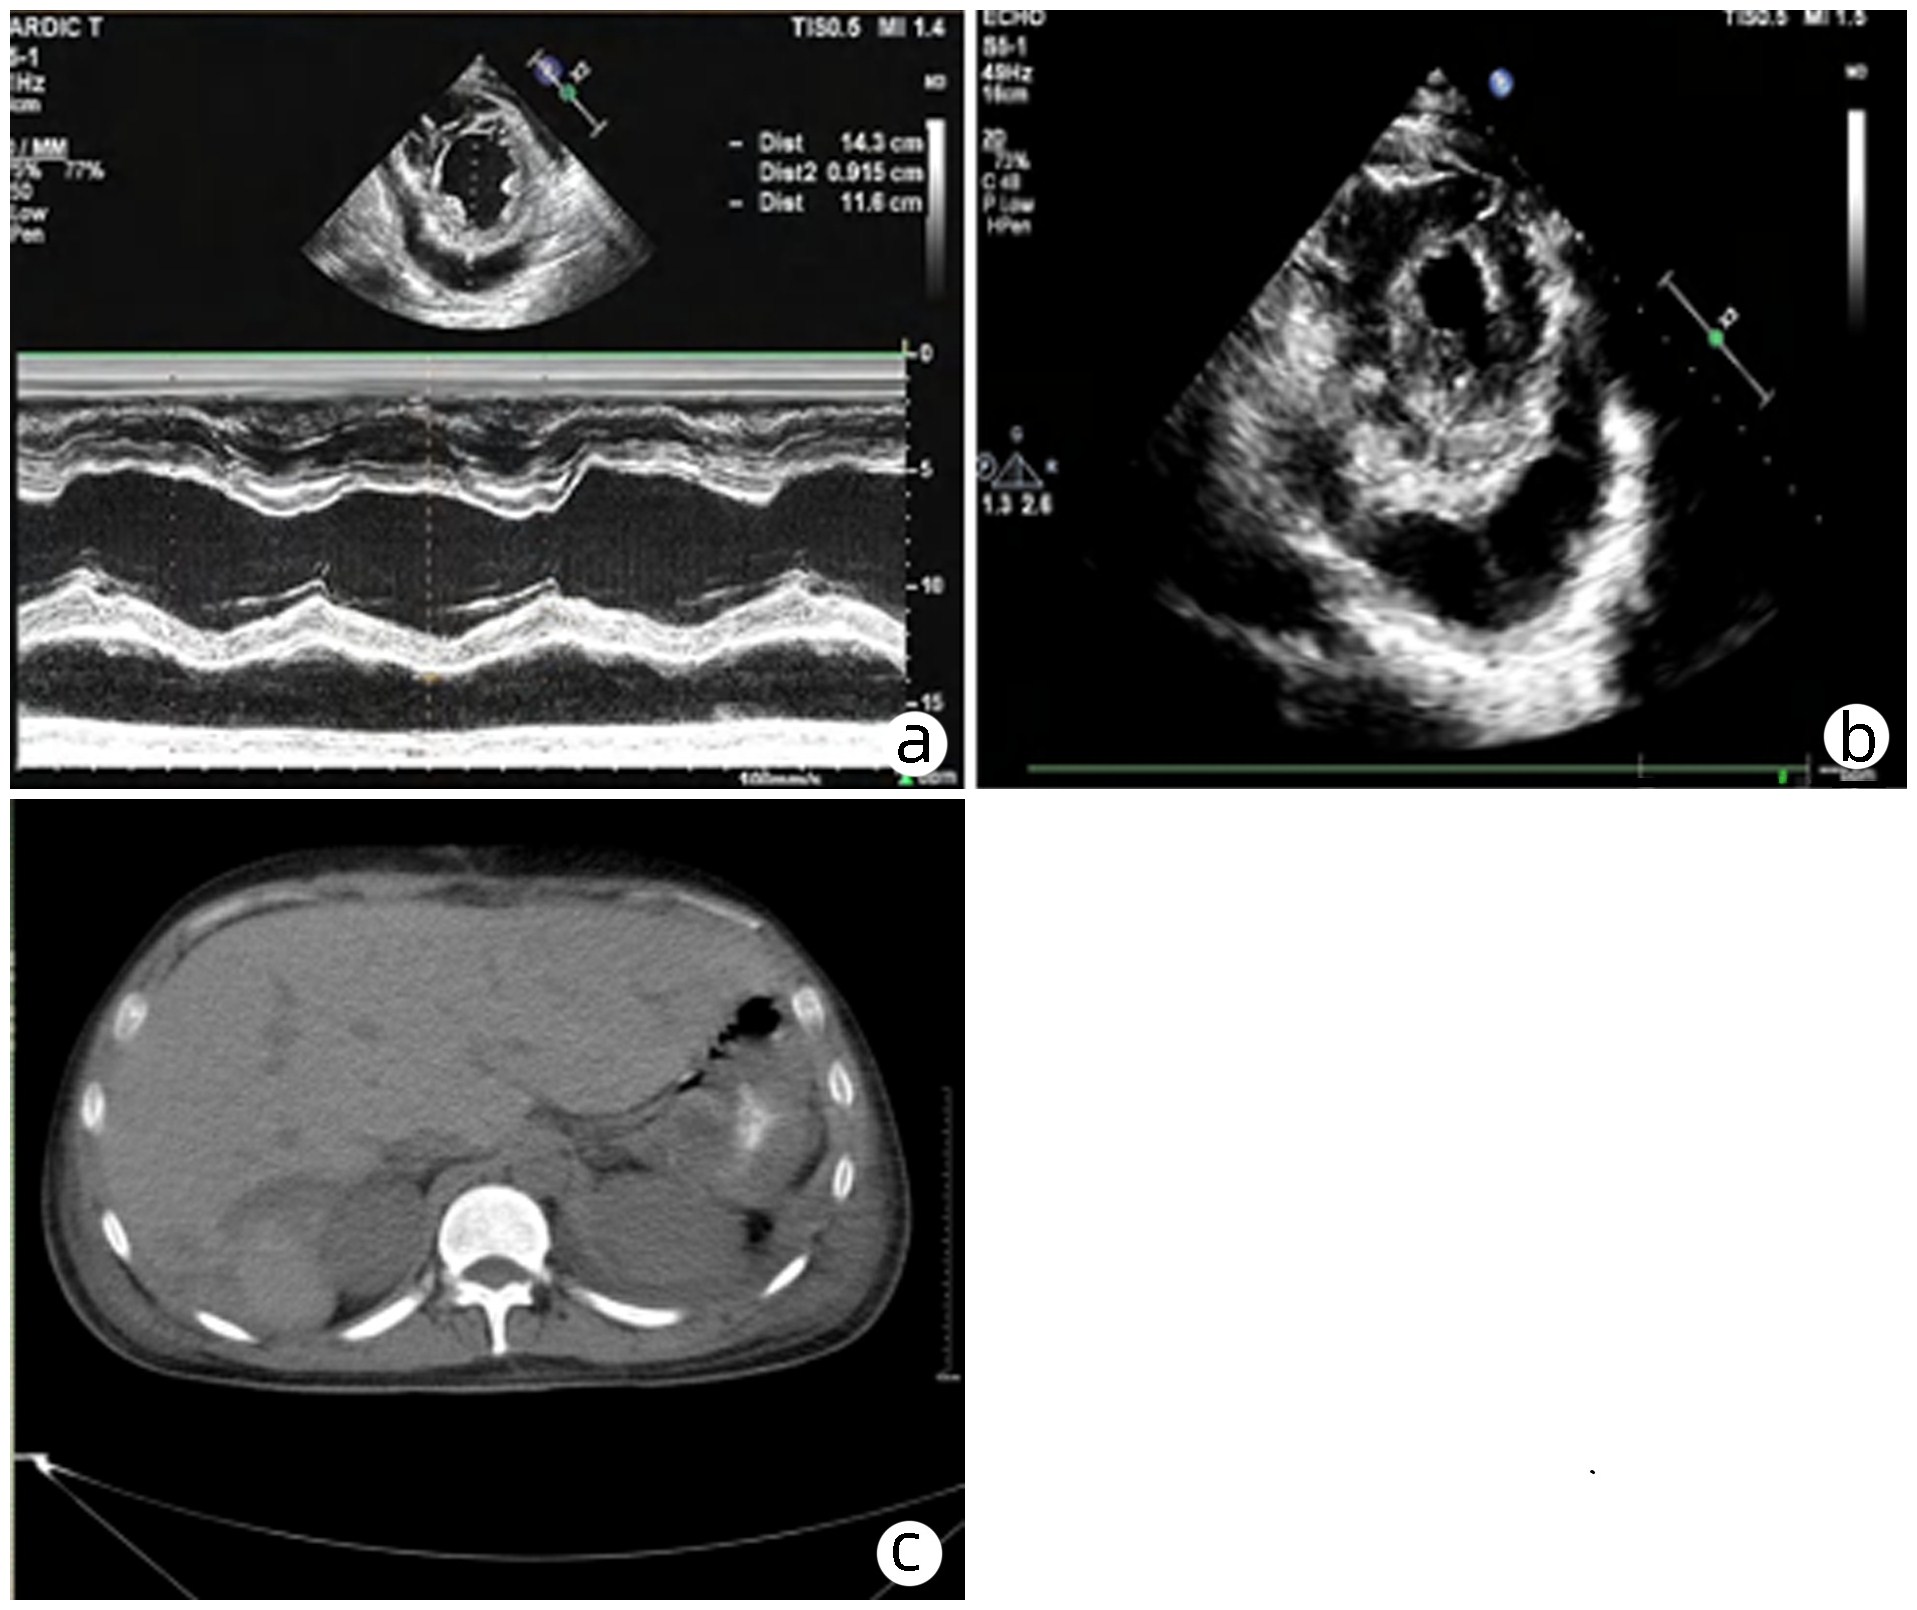

脓毒症合并自发性脾破裂出血1例报告

柳舟, 夏文芳, 詹丽英, 方小雨, 张亮, 詹娜, 禹荣, 黄丽, 朱垒

2023, 39(8): 1926-1931. DOI: 10.3969/j.issn.1001-5256.2023.08.024

摘要(1291) HTML (293) PDF (4249KB)(99)

摘要:

脓毒症所致重症感染往往导致多器官功能不全,如心功能不全、肾功能不全、肝功能损伤、脓毒症脑病、凝血功能障碍等。严重感染不仅导致全身炎症反应风暴,同时可诱发脾脓肿形成,甚至自发性脾破裂出血。自发性脾破裂起病隐匿,症状不典型,通常无明显外伤病史,临床容易漏诊。本例脓毒症患者突发左上腹疼痛、血红蛋白进行性下降,紧急完善腹部CT检查,考虑脾破裂出血。剖腹探查术术中发现腹腔大量积血,脾周血肿明显伴脾脏包膜撕裂,遂行全脾切除术。病理提示:脾脏慢性炎症细胞浸润,考虑脾脓肿伴出血。术后患者血色素平稳,腹痛症状明显好转。